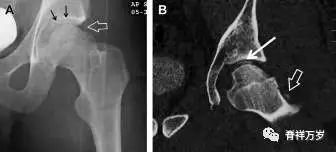

股骨颈应力性骨折

股骨颈应力性骨折在参加耐力运动的运动员中常见,且常发生在股骨颈压力侧。股骨颈基底部发现一垂直于骨皮质的线性硬化带可诊断这种类型的疲劳性骨折(图 7)。

图 7 长跑运动员股骨颈应力性骨折。X 片(A)和冠状位 CT 多维重建(B)图像示穿过股骨颈内侧皮质中的透亮区(箭头),周围硬化。骨折垂直于皮质

股骨颈张力侧的应力性骨折有可能发展为完全骨折(图 8)。

图 8 进食障碍患者股骨颈应力性骨折的张力侧。A 正位片示股骨颈完全骨折。B 2周前的 X 片示局部骨量减少,正是后来发生骨折的位置(箭头)